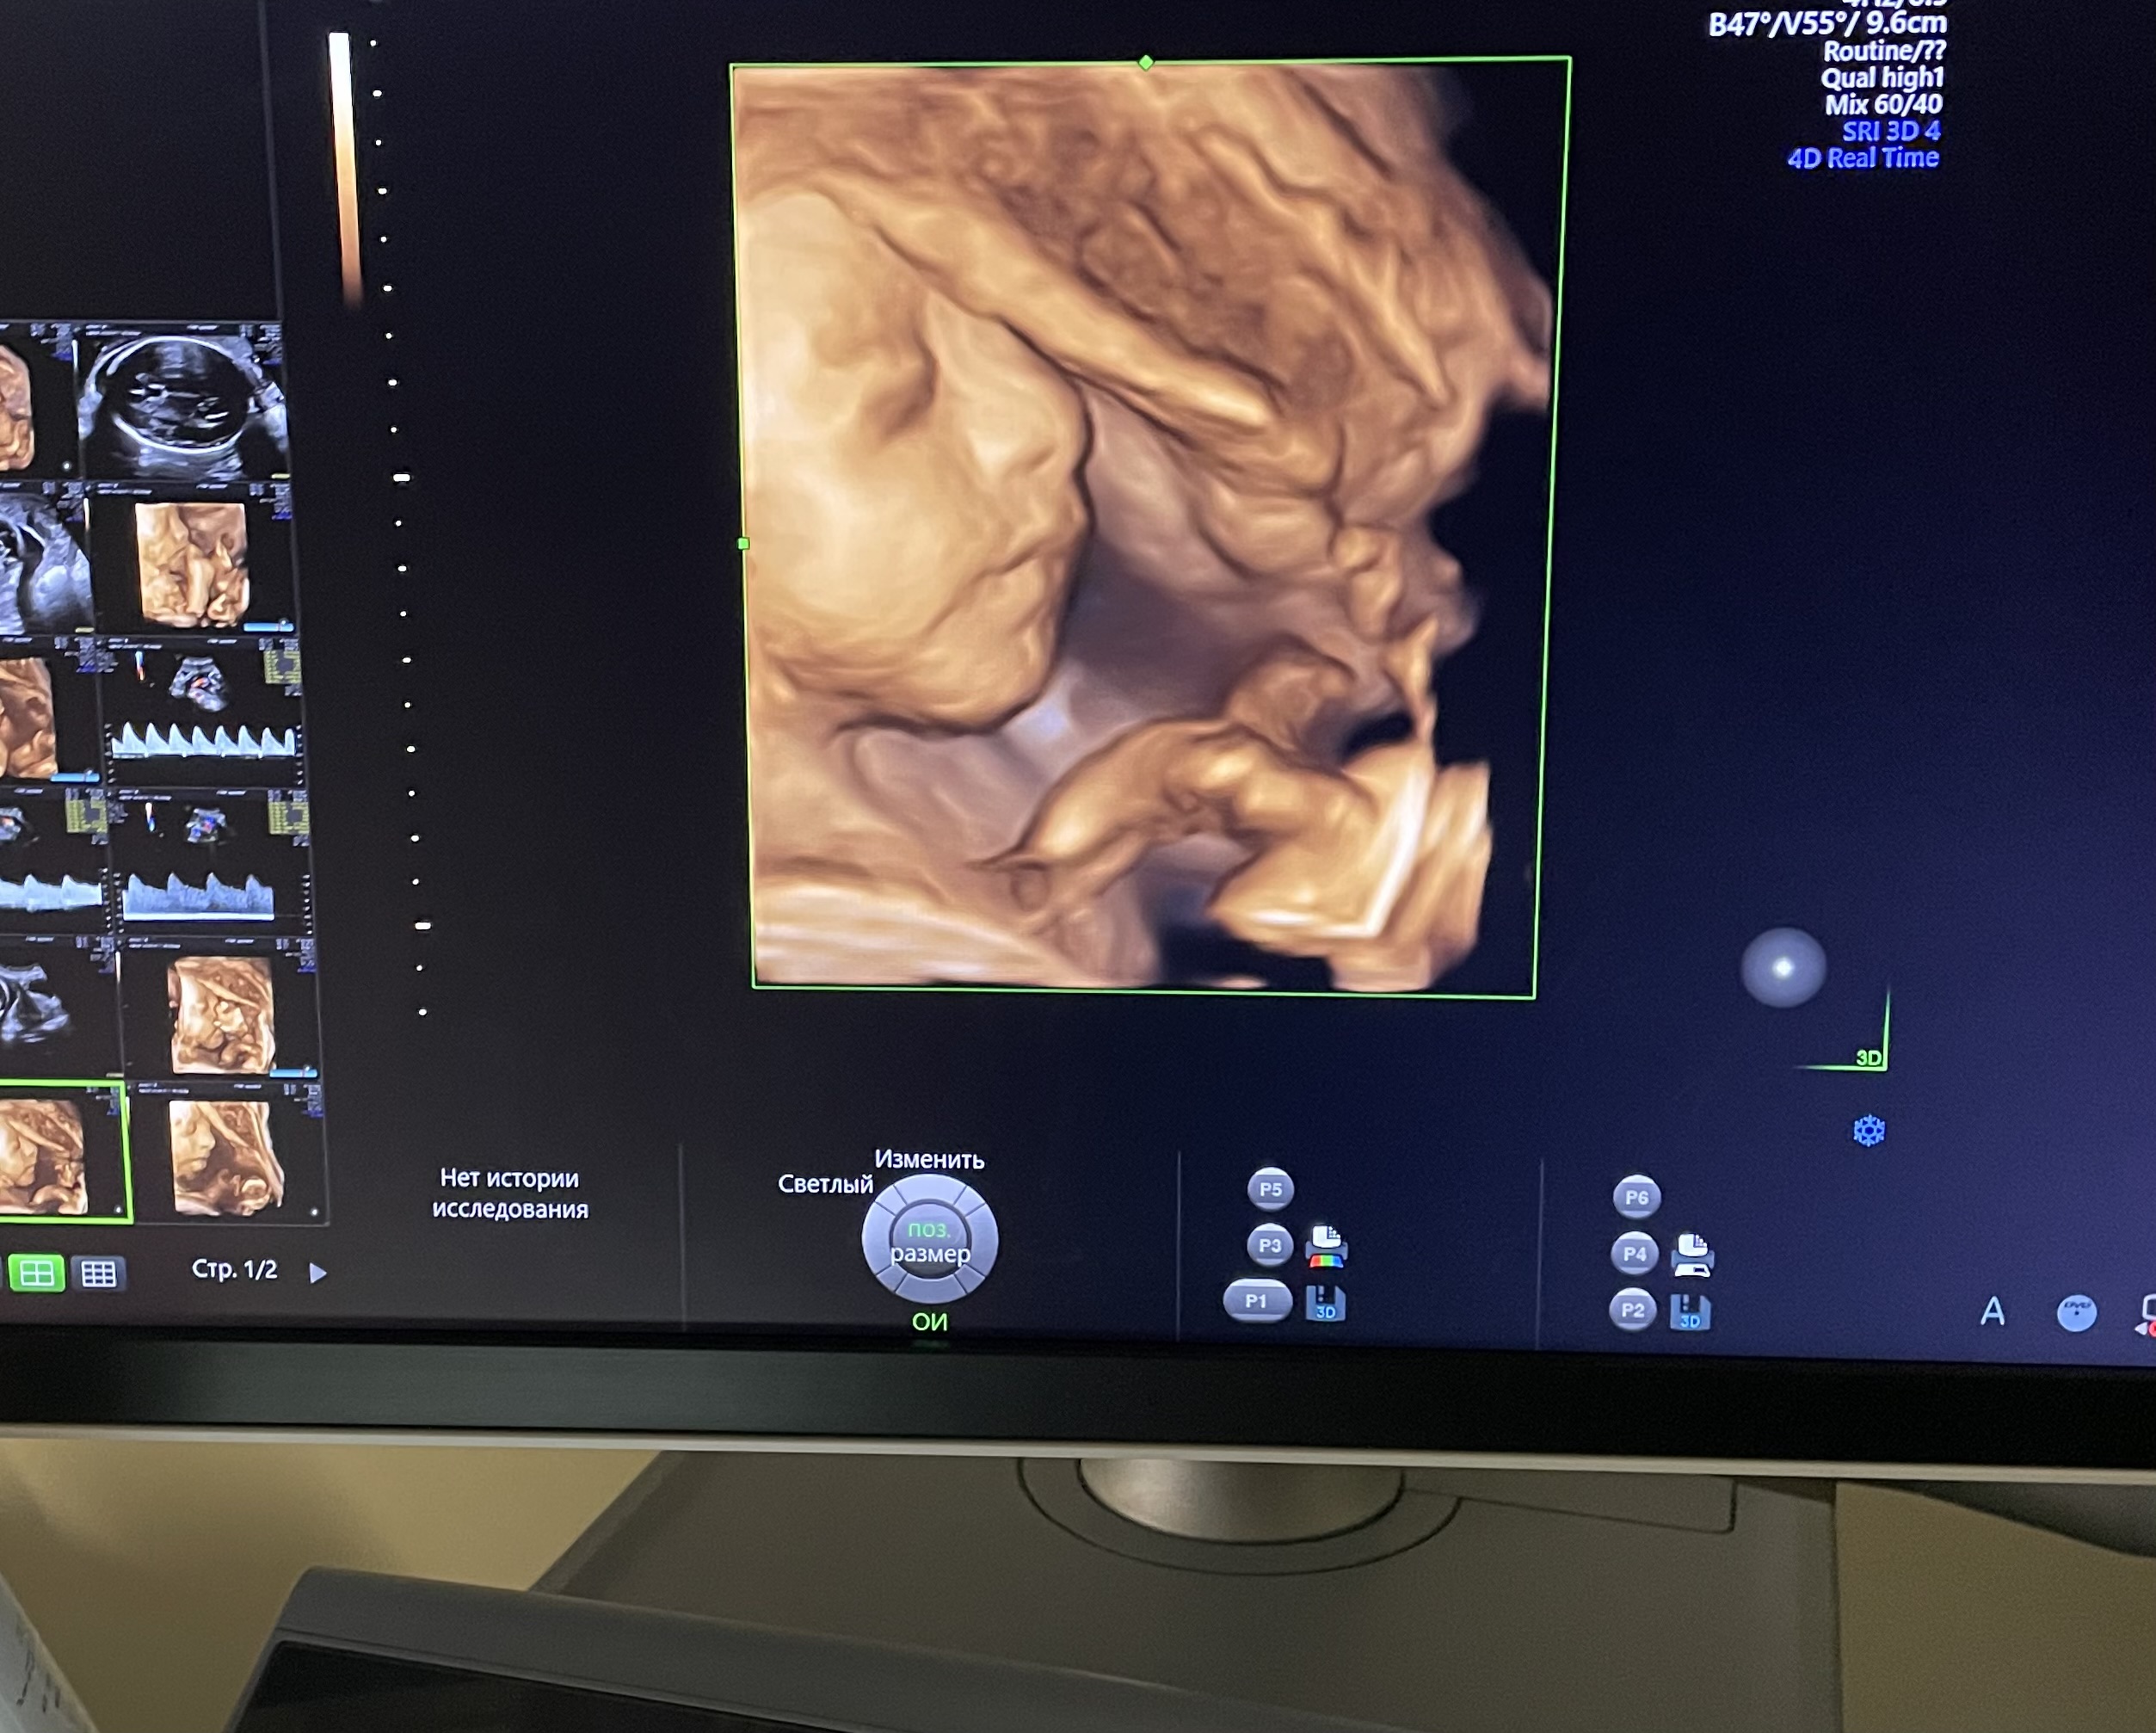

Ровно 26 недель 🤍3Д узи)))

Всё о нашей беременностиОй эмоции переполняют, смотрю и смотрю на эти фото) кто сомневается делать или нет - делайте!)🥰

по узи все хорошо, вес уже 855гр. БР - 63, ЛЗР - 86, ОЖ - 210, ОГ - 236, БК - 48, ПК - 43. Плацента поднялась наконец-то, можно больше не переживать 👌

Алла, ну вообще нужно было заплатить 5900, еще должно было быть видео на флешке. Но так мой малыш не хотел убирать ручки от лица. Она словила всего лишь пару кадров. И по итогу мне предложили оплатить как обычное узи 2650+500 за одно фото (оно с обратной стороны клеится). Ну и дали пофоткать с экрана и чб варианте тоже распечатали кадры)☺️